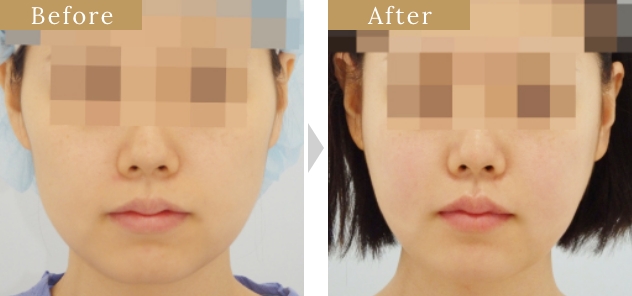

症例

小木曽クリニックの

『頬骨形成骨切り術』の特徴

頬骨体部から弓(アーチ)

部に至る広範囲な骨切りが

可能

骨切り部位は頬骨弓部から体部前面に至り、L字型に長く幅広く切除し頬骨全体を内下方へ移動するため、頬骨全体に縮小効果があります。L字型に合計4回の骨切りが必要なため、複雑で精密な手技が必要な施術です。